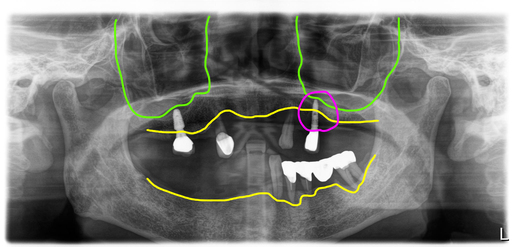

오늘 설명해 드릴 사례는 60대 여성 환자로 예전에 식립한 임플란트 중 한 개가 임플란트주위염이 생겨 뼈가 거의 다 녹았고, 나머지 남아있는 치아들도 모두 흔들거려 전체임플란트로 치료하기로 했어요.

여러 개의 치아들이 이미 상실되어 있었고, 남은 치아들은 치아뿌리의 염증이 있거나 치주염으로 이미 많이 흔들리는 상태였습니다.

그리고 예전에 식립해 둔 임플란트 중 한 개가 임플란트 주위염으로 상태가 좋지 않았습니다.

그러나 전반적인 가용골은 충분하신 상태여서 복잡한 뼈이식없이 전체임플란트 진행이 가능할 것으로 보였습니다.